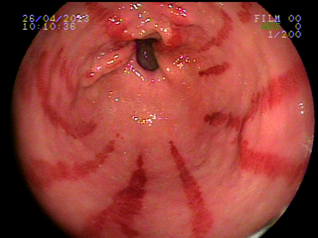

Ectasiva Vascular Antral